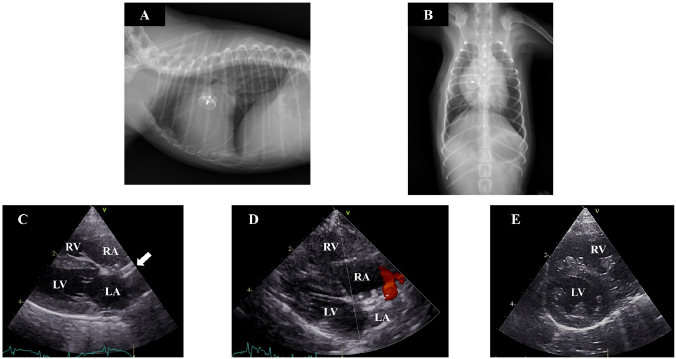

A 7-month-old female toy poodle weighing 1.4 kg was referred to the Okayama University of Science Veterinary Teaching Hospital with cardiac dilatation. The dog was maldeveloped. No cardiac murmur was detectable through thoracic auscultation, and there were no respiratory abnormalities. Complete blood count and serum biochemical test results were within reference ranges. Thoracic radiography revealed a right-sided cardiomegaly, pulmonary overcirculation, and main pulmonary artery enlargement without any tracheal, bronchial, or pulmonary abnormalities or lesions (Fig. 1a and b). Electrocardiography revealed a right-axis deviation (–150°) as well as a deep S-wave (–1.5 mV) and no arrhythmia. Echocardiography evaluation revealed moderate dilatation and concentric hypertrophy of the RV with ventricular septal flattening, enlargement of the right atrium (RA), and main pulmonary artery enlargement (pulmonary artery-to-aorta ratio: 1.34). A secundum-type ASD was also observed, and the blood flows though the defect exhibited a left-to-right shunt (Fig. 1c–e). The size of the defect was 3.3–4.0 mm, and the pulmonary blood flow/systemic blood flow ratio (Qp/Qs) as determined through echocardiography was 3.03. Based on these observations, the isolated secundum-type ASD was diagnosed. Due to the risk of progression of pulmonary hypertension, heart failure, or right-to-left shunt, ASD closure using an Amplatz canine duct occluder was planned.

Fig. 1. Thoracic radiography and echocardiography on the first examination. (a) and (b): Thoracic radiography revealed a right-sided cardiomegaly and pulmonary artery enlargement without any abnormality in the respiratory tract. (c)(e): Echocardiography revealed left-to-right shunting ASD and eccentric and concentric hypertrophy of the right ventricle with ventricular septal flattening. (ASD): atrial septal defect; (LA): left atrium; (LV): left ventricle; (RA): right atrium; (RV): right ventricle.